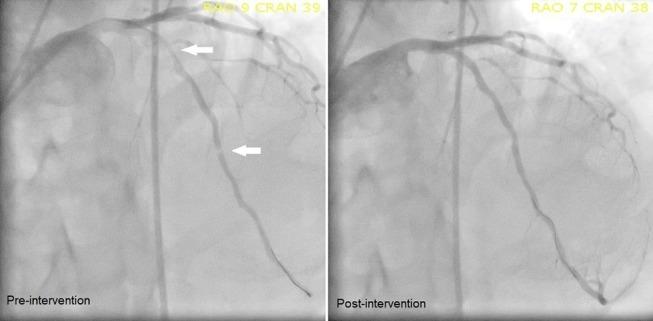

Chen Tony

Internal Medicine, University of Michigan Health System, Ann Arbor, Michigan, USA.

BMJ Case Rep. 2017 May 27;2017:bcr-2017-220621. doi: 10.1136/bcr-2017-220621.